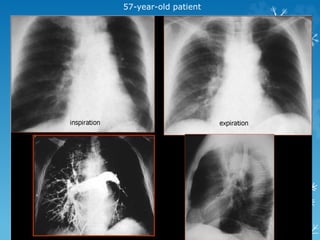

57-year-old patient

K/C/O AML ontreatment

HRCT chest revealsbilateral diffuse GGO with air space consolidation and subpleural sparing and a few air cysts classical of Pneumocystis jiroveci pneumonia Pneumocystis jiroveci pneumonia (PCP)